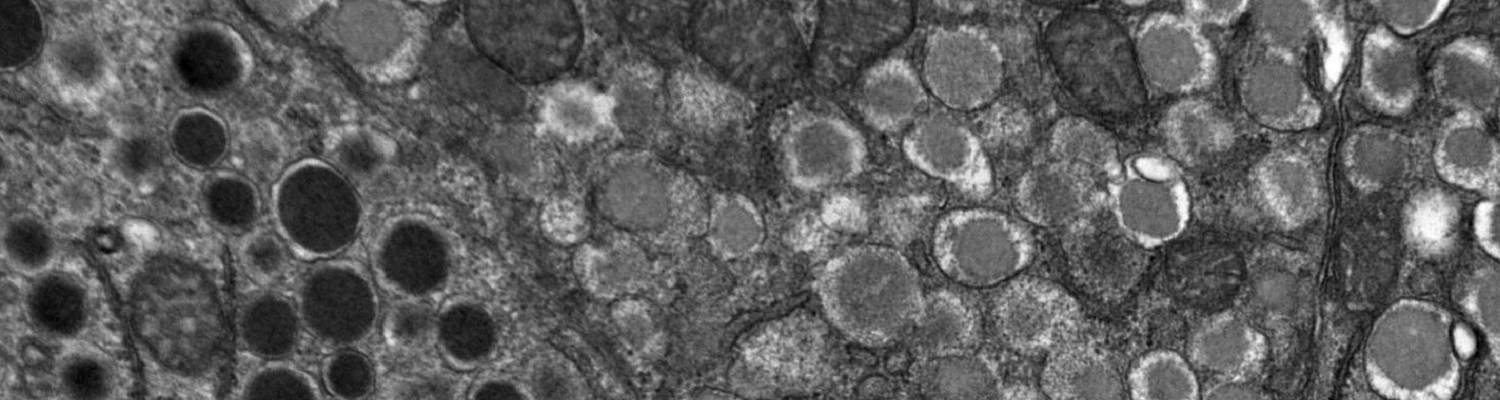

- Lack of understanding of the biology of how human insulin-secreting beta cells die during the development of T1D.

- How human beta cells resist killing by a human immune system in vivo

- How human beta cells replicate and regenerate in vivo

- How a human immune system targets and kills beta cells in vivo